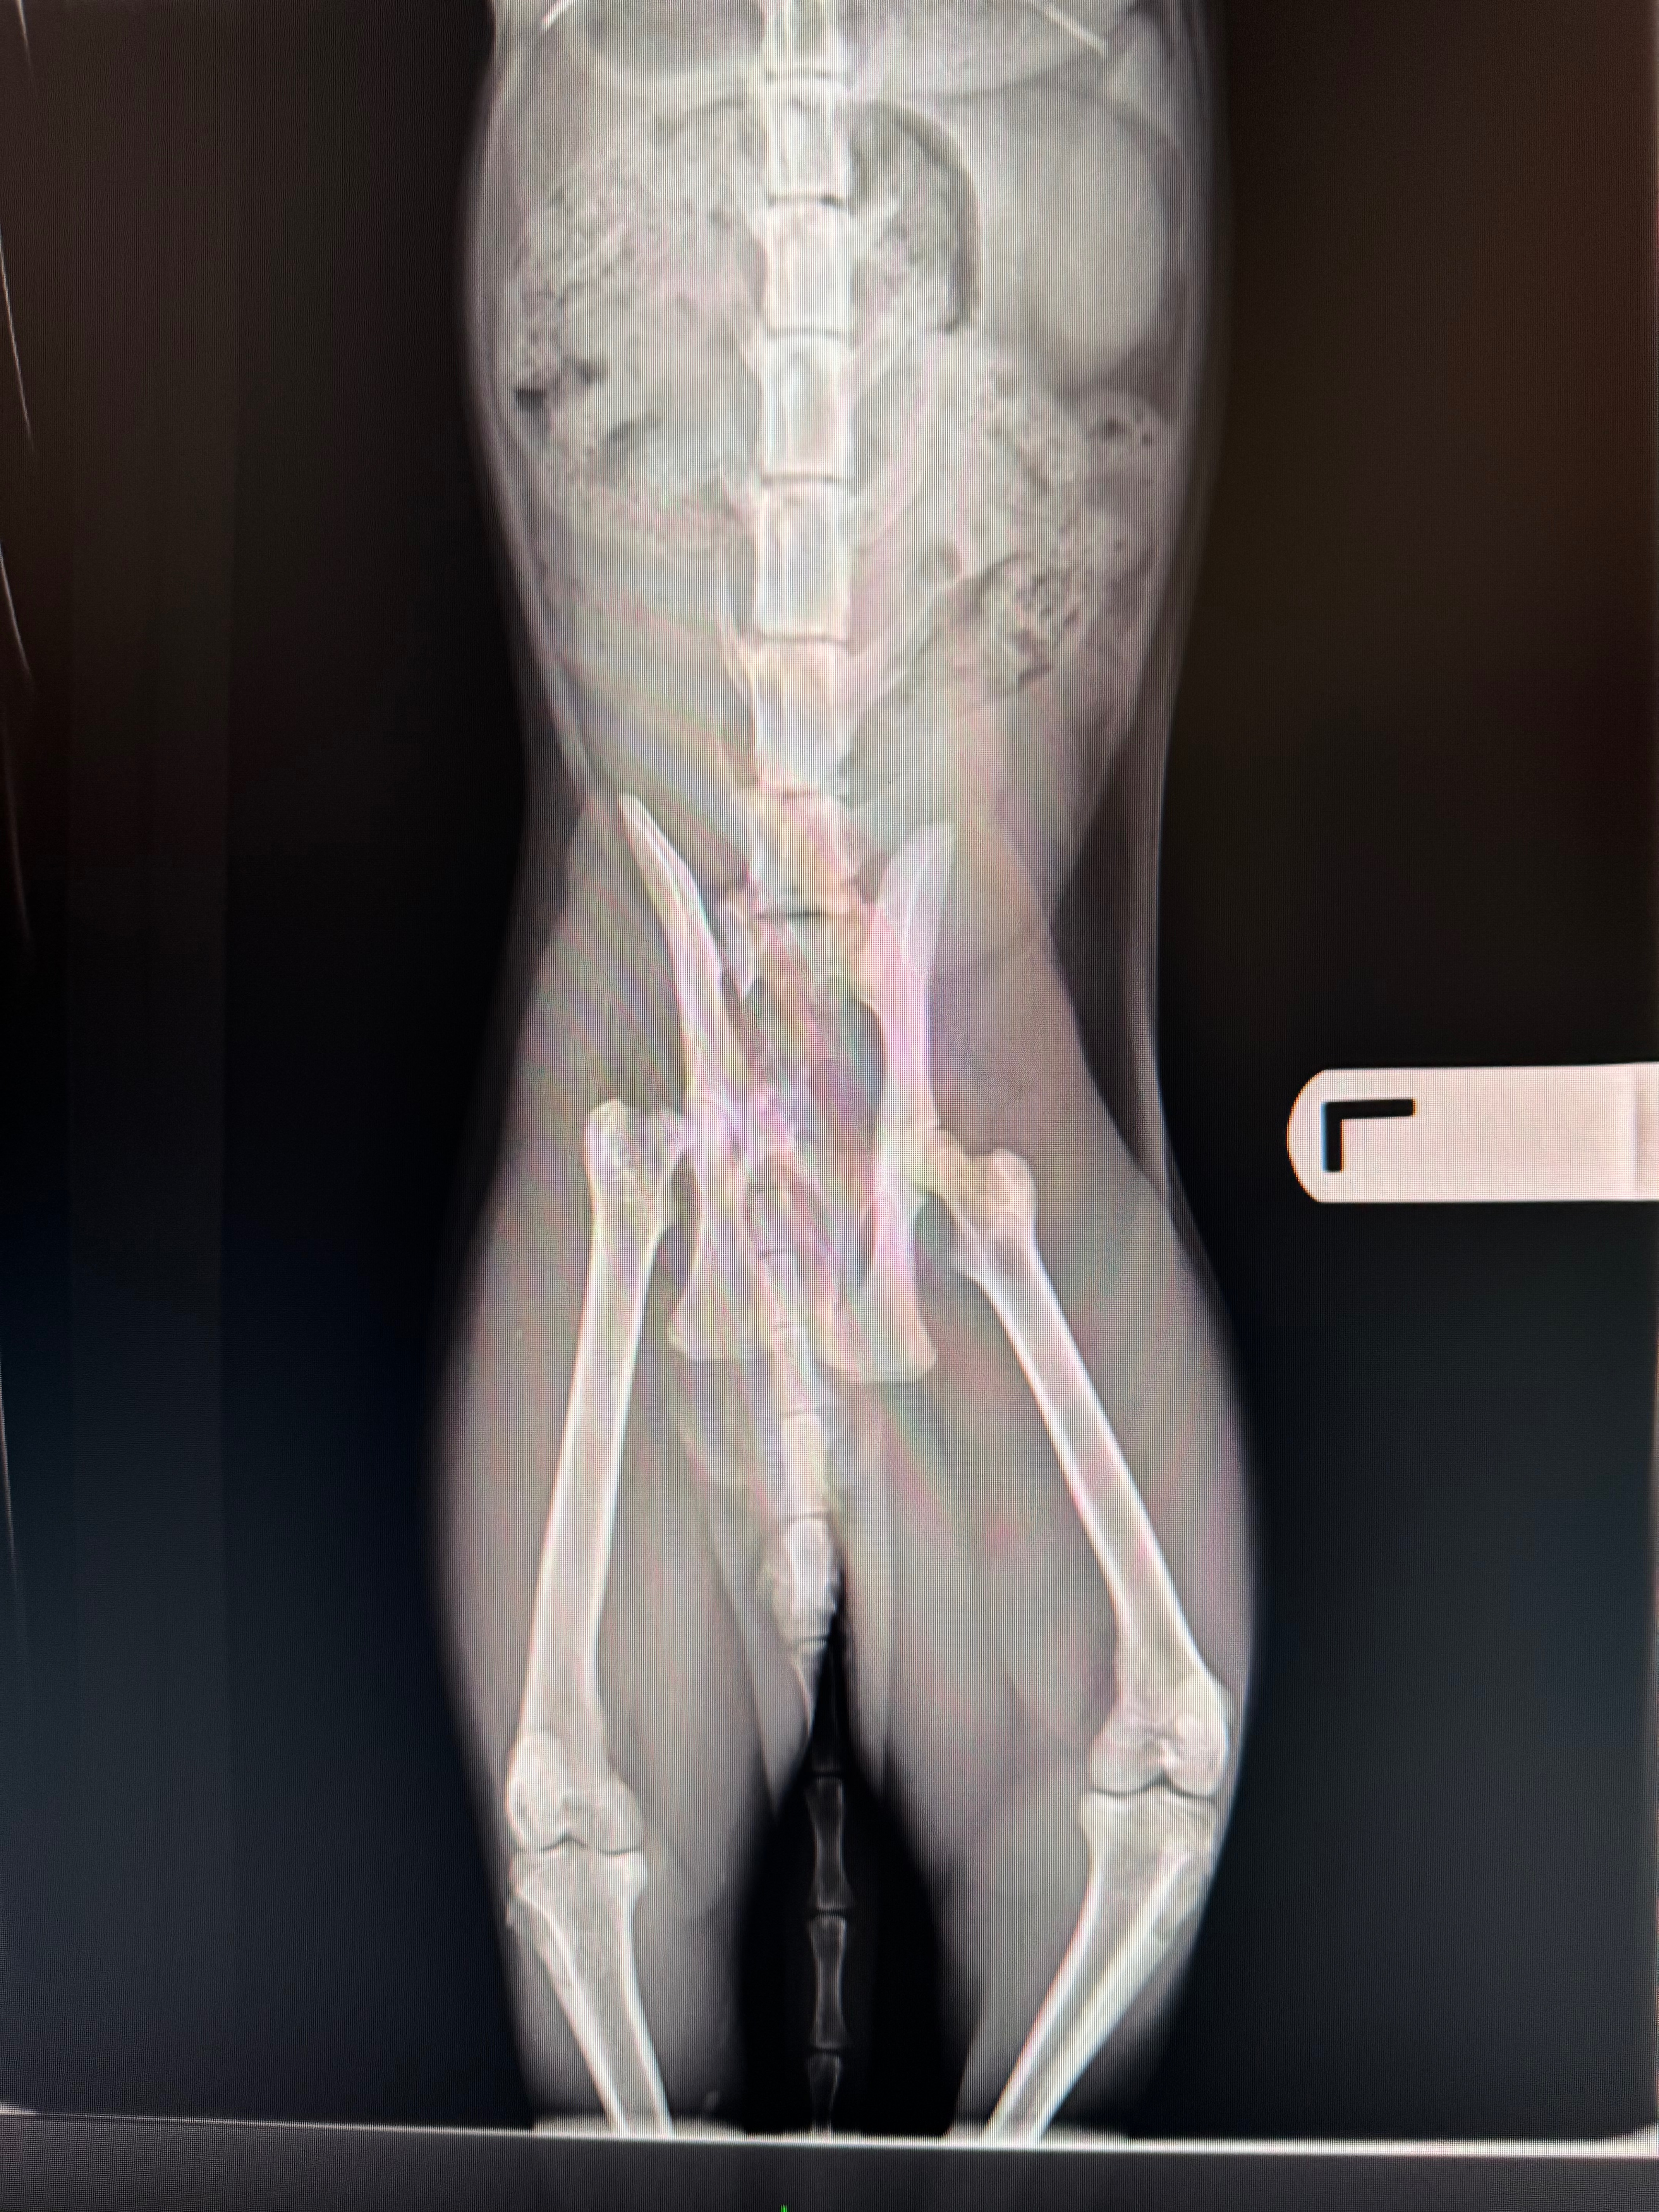

This morning, my sweet cat Parker was hit by a car. He suffered a fractured femur and pelvis, road rash abrasions, and is currently urinating blood. He’s in pain but stable—and the vet says he needs immediate surgery to have any hope of walking again.